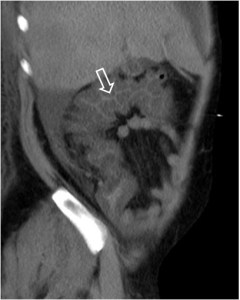

Signo de edema o inflamación severa del colon, de cualquier etiología, visto en TC. Corresponde al engrosamiento de la pared del colon con retención del contraste oral entre las haustras engrosadas (flevchas), aunque el signo también puede estar presente en TC sin contraste. Fue descrito inicialmente en la colitis por Clostridium difficile (colitis pseudomembranosa), pero después se ha demostrado que no es específico, pudiendo estar presente en otras colitis infecciosas por otros gérmenes (Salmonella, citomegalovirus,…) en colitis isquémica, en vasculitis (lupus) e incluso en el edema relacionado con cirrosis.

Otras imágenes del signo en otro paciente. Cortes axial (derecha) y sagital (izquierda), donde se observa la afectación del ángulo hepático del colon.